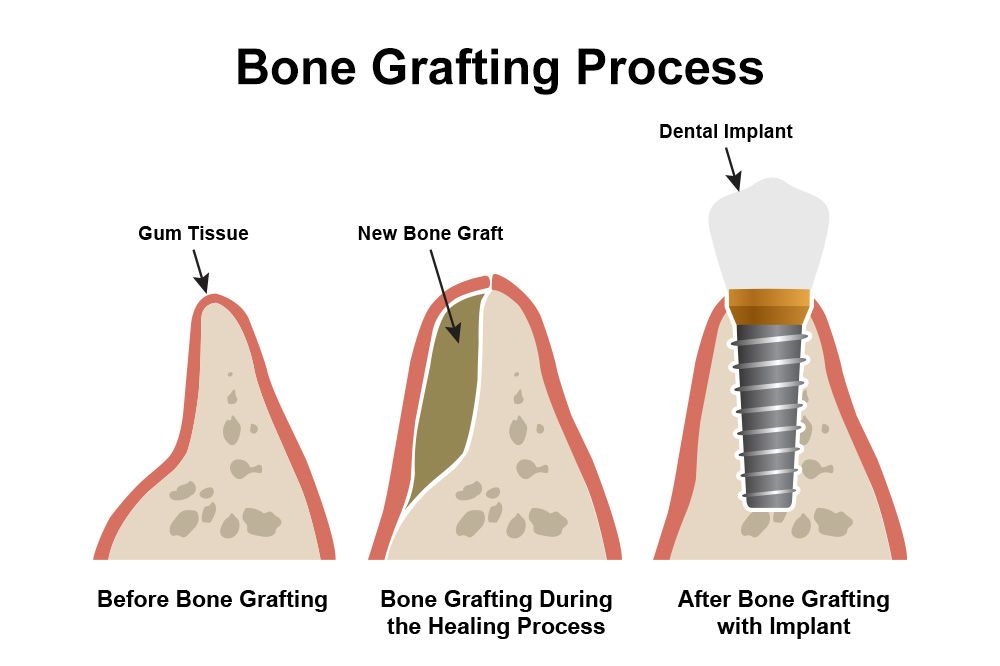

Treatment timelines vary based on individual needs, healing time, and whether bone grafting is required.